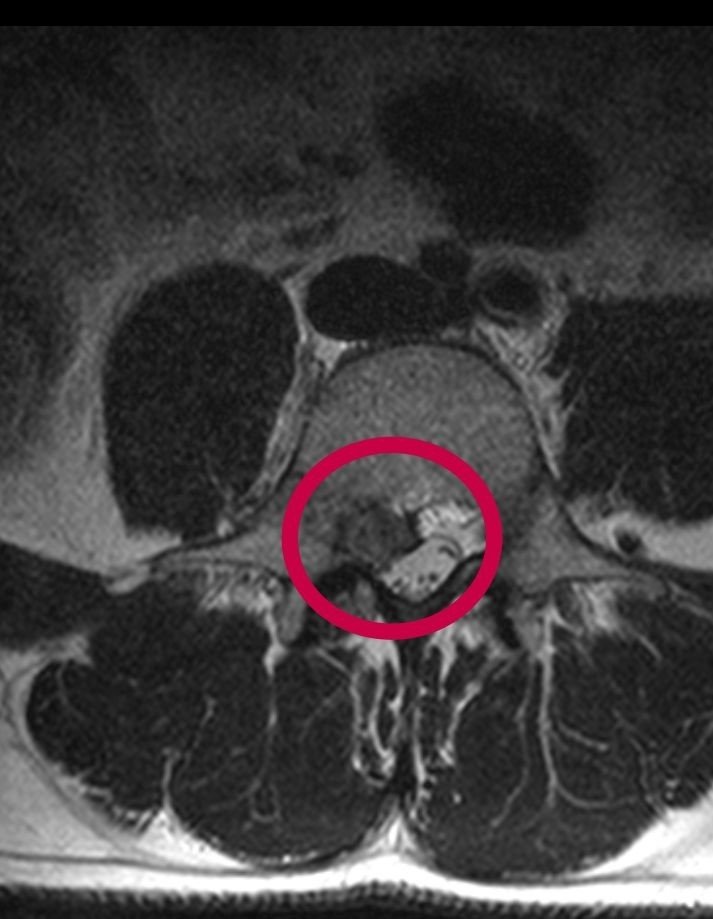

Düzce Üniversitesi Hastanesi'nin başarısı ülke sınırını aştı. 23 yıldır İskoçya'da yaşayan ve orada kuaför olan 40 yaşındaki Yasin Emre Meydan çektiği ağrılardan Düzce'de kurtuldu. Yaşadığı İskoçya'da rahatsızlığına bir türü çözüm bulamayınca tatil için geldiği memleketi Düzce'de, Düzce Üniversitesi Hastanesi'nde yapılan tetkikte bel fıtığı olduğu tanısı konuldu. Düzce Üniversitesi Tıp Fakültesi Hastanesi Beyin ve Sinir Cerrahisi Anabilim Dalı Doç. Dr. Cengiz Tuncer'in yaptığı başarılı ameliyat ile Yasin Emre Meydan sağlığına kavuştu.

Doç. Dr. Cengiz Tuncer de "İskoçya'dan bel fıtığı tanısı ile ameliyat olmak için Düzce'mize gelen hastamızın operasyonunu başarı ile tamamladık" dedi.